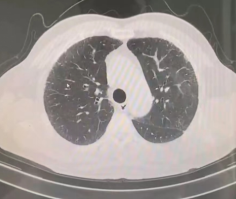

▲2019年胸部CT显示,少许间质性肺炎

(画圈处)改变